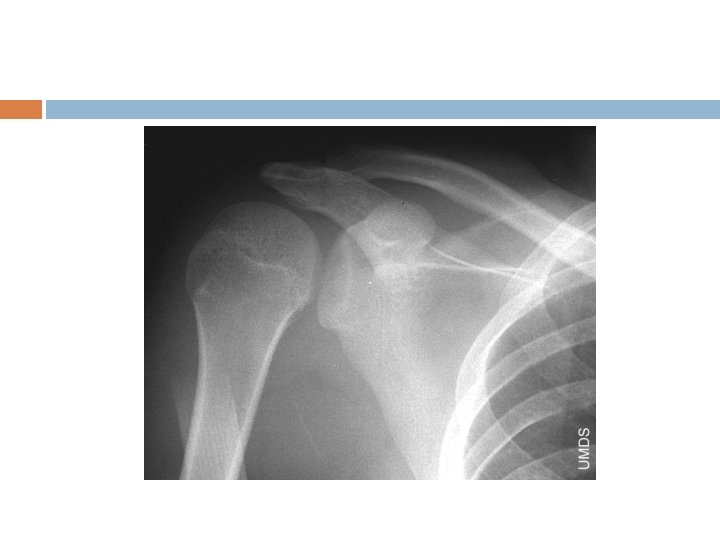

Posterior Dislocation Much less common Flexion, adduction, internal rotation- offensive lineman “Lightning strikes and seizures” Easy to miss, especially on AP film Reduction is more difficult- apply traction in line and try to manipulate humeral head back into place

Anterior Instability Exams-Apprehension -Relocation -Load and Shift Diagnostics-X-ray Views: AP, axillary and scapular-Y -can be performed before for diagnosis or after reduction for confirmation of relocation depending on clinical setting